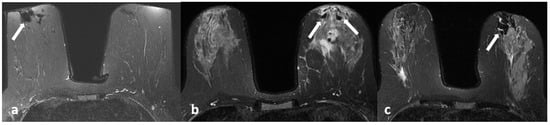

Figure 5.

A 42-year-old woman with histopathologically proven invasive ductal carcinoma involving the left breast. (a,b) Contrast-enhanced subtracted images show segmental enhancement with clumped internal enhancement pattern extending into the nipple in the left breast.